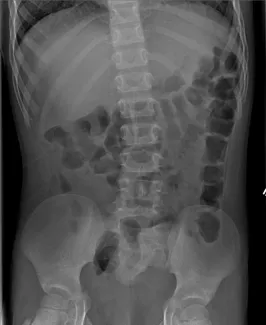

Abdominal Xrays are necessary to evaluate the effectiveness of the laxative or enema therapy and to identify the amount of stool in the colon. These will be done at each office visit.

Firm bowel movements can be painful to pass. This can lead to stool with-holding which further worsens constipation. Blood streaks lining the firm stools may mean anal fissures, which are cracks or tears near the anus caused by passing hard stools. If this is noted, increase fluid intake and call our office to schedule a clinic visit and an abdominal Xray. The dose of oral laxatives may need be increased before the clinic visit.